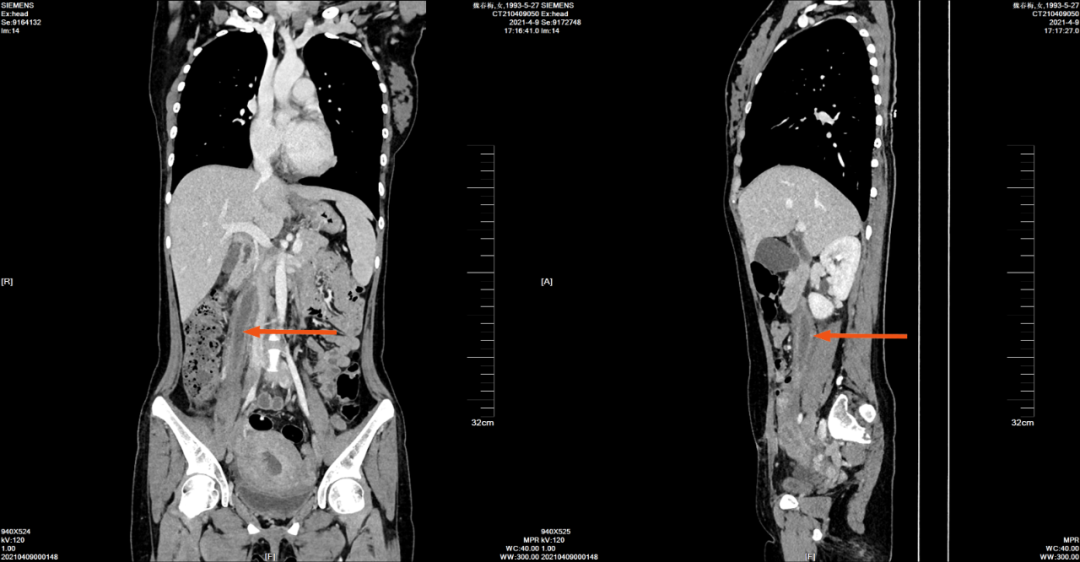

2021-4-9 腹部 CT 增强如下:

增强门静脉期

冠状位与矢状位

右侧卵巢静脉明显增粗,管腔内可见充盈缺损,右侧卵巢静脉周围可见条片稍低密度影,增强扫描卵巢静脉壁轻度强化影,与 CT210403-134 片其内密度有所减低,病灶周围渗出影有所减少。